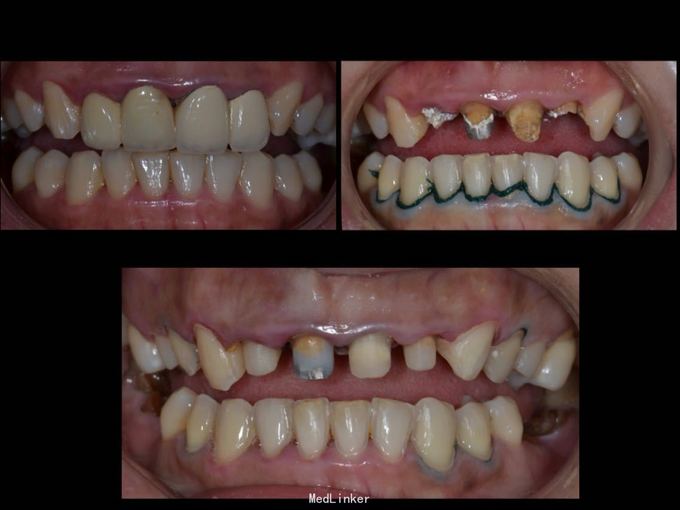

11 12 21 22死髓牙,不良修复体,牙龈炎 36 37 46 47残根 牙列不齐 处置:全口洁治。 比色,拍照,取模型做蜡型。 拆除旧修复体,拆桩核,做根管治疗,纤维桩修复,牙体预备,取模,做临时冠,粘固。11 12 21 22全瓷冠修复,13 14 23 24 31 32 33 34 41 42 43 44瓷贴面修复。

1.旧修复体覆合大,11 212 21 22龈缘位置较低且不对称,能做冠延长协调红白美学,更好 2.拆旧桩核要小心根折,用超声振动,一点一点拆.11桩核粘固比较牢固,根尖炎,定期观察行根尖手术倒充填。 3贴面的粘接,耐心